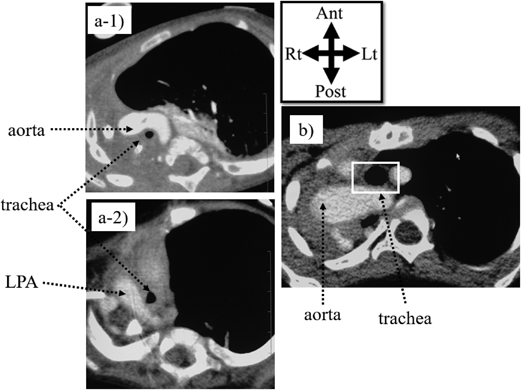

手術治療は,気管径が比較的保たれているようであれば左肺動脈を気管前方に移植し,さらに大動脈つり上げ術を追加する.気管径の拡大が必要な場合には,スライド気管形成術を適用する.また,気管形状が‘S-shape’となっていることから,スライド気管形成術と同時に気管を大動脈前方にtranslocationする術式も報告されている57).自験pseudo-ring-sling complexの2例では,いずれも左大動脈弓,右下行大動脈で狭い大動脈弓のスペースのためさらに気管が圧迫される形態で,スライド気管形成術に気管のtranslocationを併用して有効だった(Fig. 6).

Pediatric Cardiology and Cardiac Surgery 37(4): 283-294 (2021)

Fig. 6 a) Axial view of pseudo-ring-sling complex on preoperative computed tomography. a-1) Aorta traversing anterior to the trachea. a-2) Left pulmonary artery (LPA) passing posterior to the trachea. b) Axial view on computed tomography after tracheoplasty with anterior translocation of the trachea

Note the aorta traversing posterior to the trachea. LPA, left pulmonary artery